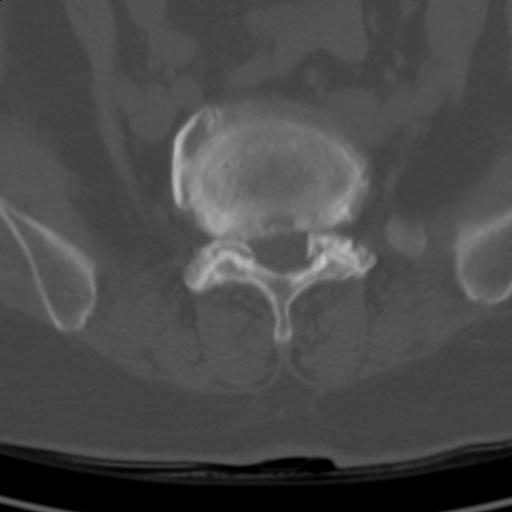

患者;女性;左下肢疼痛。

l5s1显示椎间盘突出,椎体边缘骨质增生,双侧黄韧带钙化。(请上传骨窗)

l5s1显示椎间盘突出,椎体边缘骨质增生,双侧黄韧带钙化 ,两侧椎小关节肥大,关节面硬化,关节间隙变窄,提示:椎小关节综合症

双侧的侧隐窝有狭窄。

我认为应该考虑为:l5s1椎间盘膨出,余(椎小关节退变、黄韧带钙化、椎间孔狭窄)与各位同行无异议。

l5s1显示椎间盘膨出,突出,椎体边缘骨质增生向后压迫硬膜囊,双侧黄韧带钙化,小关节面综合征